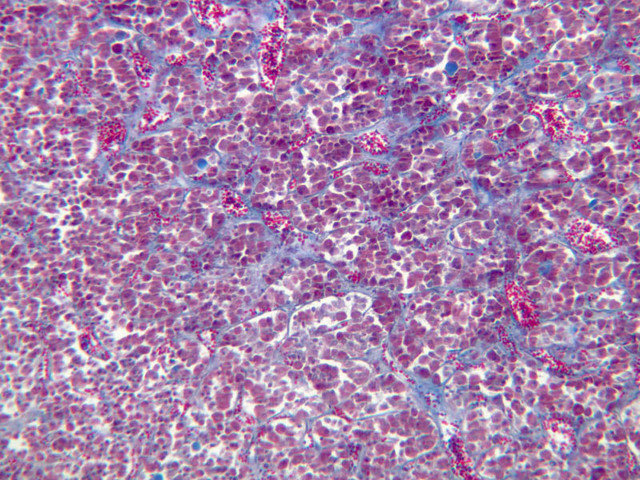

Examine slide B-56 (H&E [2.5x, 10x, 20x, 40x-labeled] [10x, 20x, 40x-labeled] [20x, 40x] [10x, 20x, 40x-labeled] [10x, 20x, 40x]). The connective tissue capsule of each parathyroid gland is continuous with that of the thyroid gland. It extends into the substance of the gland, dividing it into poorly defined lobules. Fat cells may separate the groups of cells and increase with age. Note the rich capillary network. The parenchyma is composed of two types of cells: (1) Principal or chief cells and (2) oxyphil cells. The polygonal chief cell is by far the more numerous cell type. Its nucleus is centrally located and has a vesicular chromatin pattern with a prominent nucleolus and its cytoplasm stains rather lightly. Oxyphil cells, which are less regular in shape and considerably larger than chief cells, are scattered singly or in small clusters. Their nuclei are smaller and more condensed than those of the chief cells and, owing to a very rich complement of mitochondria, their cytoplasm is distinctly acidophilic.